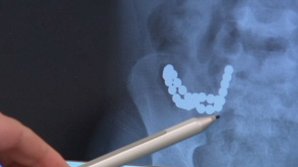

A înghițit 30 de MAGNEȚI de frigider! Medicii au rămas ÎNMĂRMURIȚI când au văzut radiografia băiețelului de 5 ani